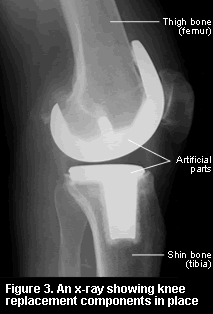

Knee joint replacement surgery may be total where both sides of the knee joint are replaced, or uni-compartmental where only one side of the knee joint is replaced. The procedure is performed by separating muscles and ligaments around the knee to expose the knee capsule, and then the inside of the joint.

Unicompartmental knee arthroplasty is a minimally-invasive procedure to replace one of the knee’s three parts (thighbone, shinbone, or kneecap) to restore function. Because only part of the damaged knee is replaced, it is often called a partial knee replacement.

If arthritis affects only one side of your knee – usually the inner side – it may be possible to have a half-knee or unicompartmental replacement (sometimes called hemiarthroplasty) (see Figure 4). The unicompartmental operation is only suitable for about 1 in 4 people with osteoarthritis. This is a less extensive operation than a total knee replacement and should therefore mean a quicker recovery. In general, this type of joint provides better mobility than a total knee replacement although it is more likely that another operation will be needed within 10 years than with a total knee replacement. If a second operation is needed it would be a total rather than another unicompartmental replacement